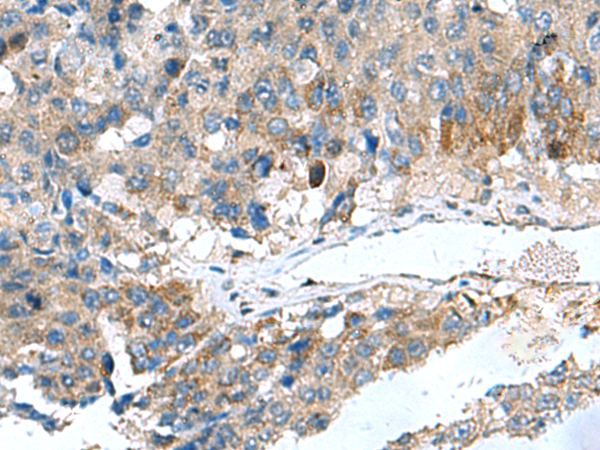

分类: 科研抗体货号: P01408别名: GLIPR; RTVP1; CRISP7应用: WB,IHC反应种属: Human, Mouse